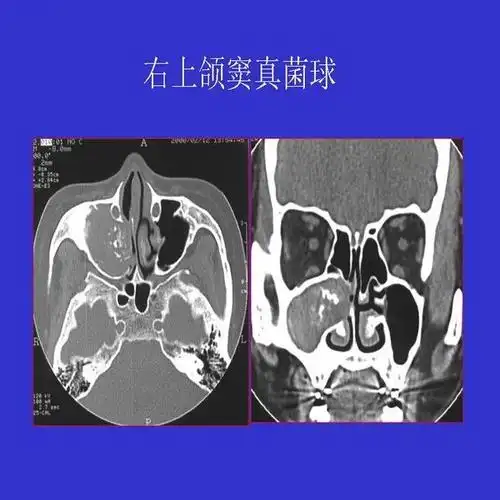

真菌性鼻窦炎影像学诊断